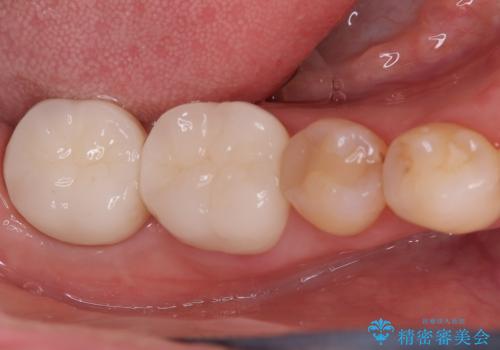

欠けやすい大きなプラスチック充填から、耐久性の高いセラミッククラウンへ

担当医 河口智英